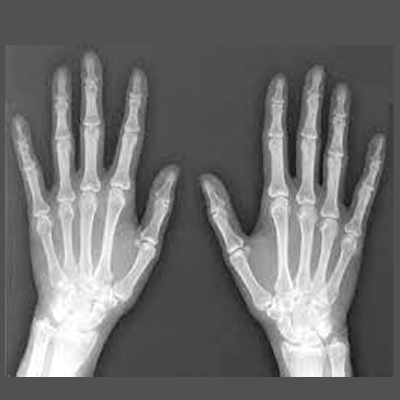

X-rays are primarily used in the medical and dental field. Some of the more common X-rays are done for broken bones and fractures, swallowed items, damage to bones from arthritis, and lung infections. X-rays are also used in a CT scanner, or computed tomography. This modality uses multiple X-rays during one scan, to give a layer-by-layer image. X-rays are also being used in non-medical areas, like airport security and by NASA in outer space.